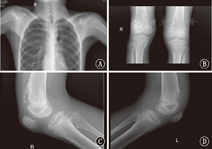

患儿,男,10岁,因"左膝关节疼痛2个月"入院,2个月前患儿无明显诱因出现左膝关节疼痛,曾就诊于外院,考虑左膝关节关节结核可能,行针灸治疗,疼痛稍好转,后家长为进一步诊治来遵义医学院附属医院。入院查体:发育正常,营养良好,生命体征平稳,左膝关节无红肿,稍压痛,屈曲背伸活动不受限,双下肢等长,四肢无畸形,X线片提示心肺未见异常,双侧肱骨上段干骺端及双侧股骨下段干骺端、胫腓骨上段干骺端见多发骨性突起,考虑多发骨软骨瘤(图1)。外院查红细胞沉降率70 mm/1 h,抗链球菌溶血素"O"(+)。初步诊断:全身多发骨病变。

注:A:胸部正位片示双侧肱骨上段干骺端多发骨性突起;B:双膝关节正位片示双侧股骨下段干骺端、胫腓骨上段干骺端见骨质破坏,多发骨性突起,关节间隙未见狭窄;C:右膝关节侧位片示右侧股骨下段干骺端、胫腓骨上段干骺端见骨质破坏,多发骨性突起;D:左膝关节侧位片示左侧股骨下段干骺端、胫腓骨上段干骺端见骨质破坏,多发骨性突起 A:the chest X-ray showed that bilateral metaphysis of proximal humerus were multiple osseous protuberances;B:the bilateral knee joint X-ray showed that bilateral metaphysis of distal femur,proximal tibia and proximal fibula were bone destruction and multiple osseous protuberances,but there was no abnormality in the joint space;C:the right knee joint X-ray showed that right metaphysis of distal femur,proximal tibia and proximal fibula were bone destruction and multiple osseous protuberances;D:the left knee joint X-ray showed that left metaphysis of distal femur,proximal tibia and proximal fibula were bone destruction and multiple osseous protuberances